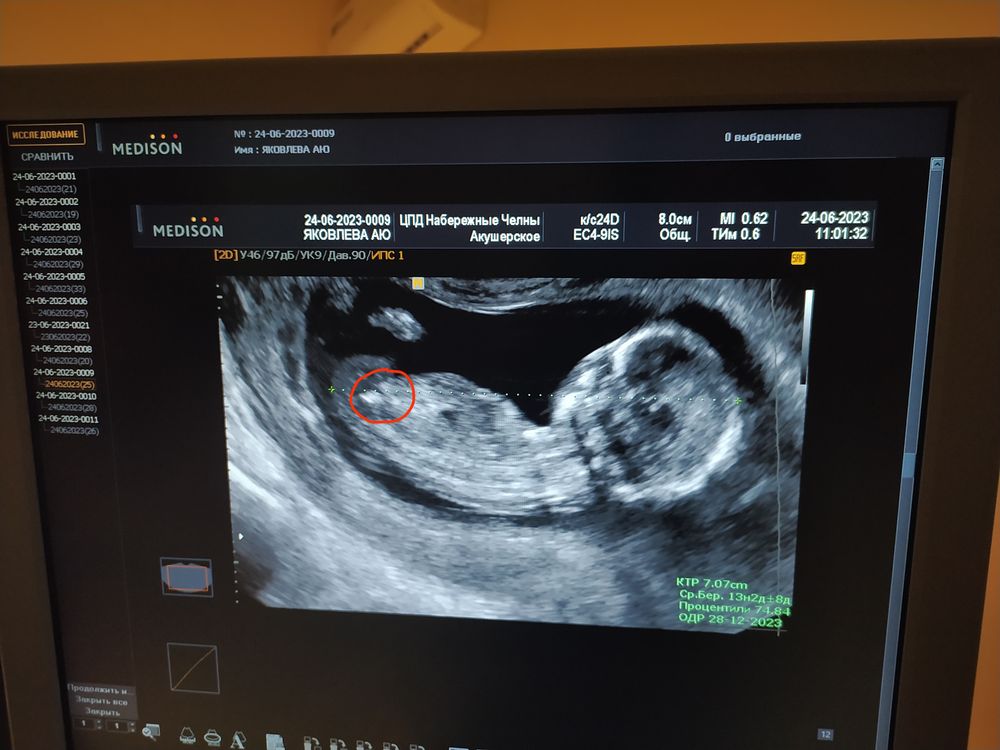

Кто понимает в узи , скажите кого ждем?) там в низу если приглядеться в районе попы то ли яички то ли яичники ) которые опустились сижу гадаю сравниваю с прошлыми узи детей все равно не понятно))

Кто понимает в узи , скажите кого ждем?) там в низу если приглядеться в районе попы то ли яички то ли яичники ) которые опустились сижу гадаю сравниваю с прошлыми узи детей все равно не понятно))

А мне кажется это девочка писюшка мальчика другая.нам прям перчики всегда показывали сразу видно

Вообще видно плохо, но мне кажется, что девочка.